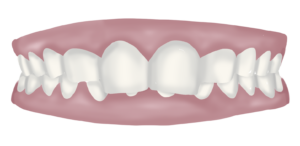

Sobremossegada

La sobremossegada es caracteritza perquè les dents del maxil·lar superior recobreixen en excés les del maxil·lar inferior. En alguns casos les del maxil·lar inferior estan completament ocultades per les del superior (no es veuen els incisius inferiors, de vegades aquests poden inclús impactar a la geniva del paladar quan tanquem).

Aquest tipus de maloclusió es considera una mossegada en desequilibri ja que, degut al fet d’haver-hi un excessiu recobriment, queden molt limitats els moviments de la boca i l’individu té gran dificultat per fer lliscar la mandíbula cap a un costat i cap a l’altre.

Aquest és un moviment necessari per a la masticació i si no es pot fer amb facilitat generem una sobrecàrrega de tota la musculatura perioral i cervical, cosa que desemboca amb dolors cervicals, dolors d’articulació temporo-mandibular (perquè també treballa en desequilibri i sobreesforç) i en alguns casos amb migranyes i acúfens.

Tota aquesta tensió muscular es pot transmetre també a la resta del cos a través de les diferents cadenes musculars que van de la boca fins als peus. Per tant, sovint trobem modificacions posturals ja que el cos, al llarg dels anys s’adapta i compensa com pot per seguir fent la seva funció.

L’activador plurifuncional que oferim en aquests casos ens procura un augment de dimensió vertical de la boca, això fa que al cap del temps es reposicioni la mandíbula en una posició molt més fisiològica, generant més espai a l’articulació temporomandibular i facilitant els moviments de lateralitat per mastegar. Això es tradueix en una reducció de les tensions tant musculars com articulars de la zona de cap i coll i també en un a reducció del dolor. Paulatinament també es va transmetent aquest canvi a la resta del cos i el consultant experimenta canvis de postura.

Per això, també incloem en aquests casos un acompanyament amb fisioteràpia de reeducació postural, a través del mètode Feldenkrais ®, i també una visita de valoració optomètrica, perquè moltes vegades aquestes tensions i adaptacions que es transmeten per cadenes musculars també afecten a l’alineació dels ulls, en alguns casos donant problemes de visió.

Quan una sobremossegada es corregeix i augmenta la dimensió vertical de la boca, l’individusent en un primer moment que està molt més còmode a nivell d’articulació temporomandibular i cervicals però que no li contacten els queixals per mastegar.

Això és completament normal i, de fet, és una senyal de que el tractament està funcionant.

En el cas dels infants, adolescents i adults joves, aquest defecte d’oclusió es corregirà de forma natural amb el poder d’extrusió que tenen les dents. Amb el temps, aquestes aniran buscant el contacte i aniran «erupcionant» per si soles fins a trobar el contacte amb les seves dents antagonistes.

En el cas dels adults, això és més difícil que passi i requereix de molt temps. Per tant, si la distància a salvar és molt gran o, sobretot, si hi ha desgast de les dents perquè hi ha antecedents de bruxisme o pròtesis realitzades amb l’antiga oclusió, caldrà rehabilitar la mossegada afegint el material necessari perquè tornin a contactar totes les dents i l’individutorni a trobar un bon apoio i equilibri oclusal. Aquesta rehabilitació es pot fer en un primer temps amb alces de composite, que col·loquem i ajustem durant les visites de control. Al final del tractament, per fer-ho de forma més definitiva i resistent al llarg del temps, es faran onlays o corones, depenent de cada cas.